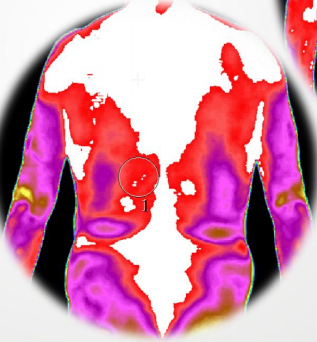

感冒后咽喉肿痛

通过图片画圈地方显示很明显的就会看出哪里出现症状。